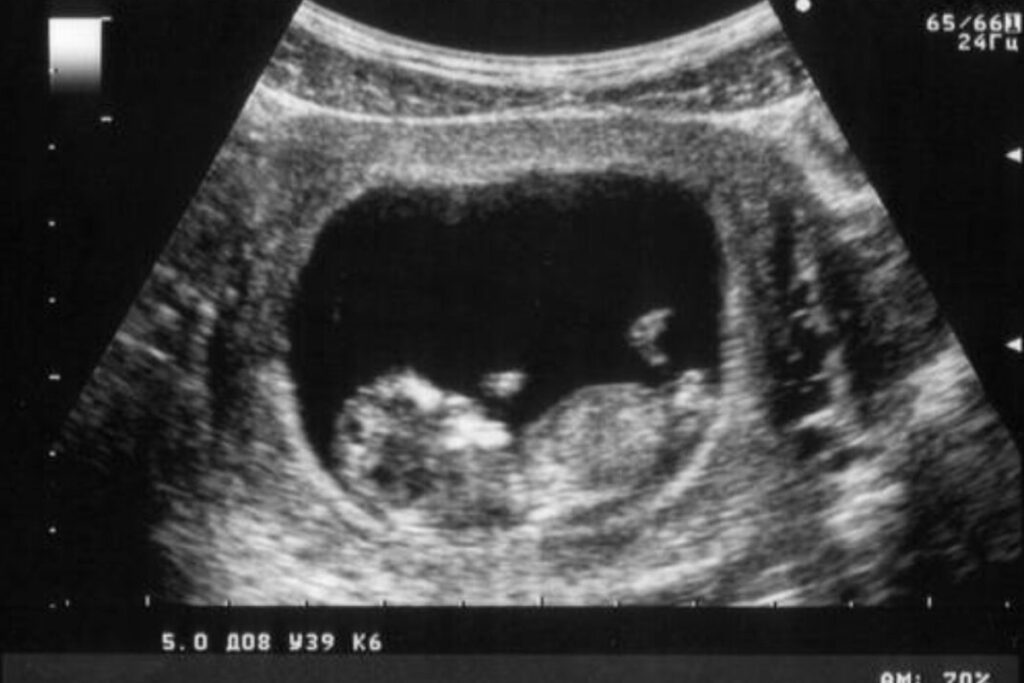

L’ordinanza, emessa dalla giudice Cristina Ferrari, accoglie le tesi degli avvocati della famiglia, basandosi su un quadro probatorio definito “inequivocabile”. Nonostante la donna si fosse sottoposta a numerosi esami ecografici – dal ginecologo di fiducia, al consultorio Ausl, fino alle visite ospedaliere – nessuno aveva rilevato la malformazione.

Nell’ordinanza si legge chiaramente: “È altrettanto pacifico e documentato che nessuno dei medici coinvolti nella vicenda avesse rilevato prima della nascita del bambino l’esistenza della malformazione, nonostante durante la gravidanza la donna si fosse sottoposta a plurimi esami”. Le perizie medico-legali hanno confermato che quasi tutte le ecografie furono lette in modo errato, indicando superficialità e mancata attenzione da parte del personale sanitario.